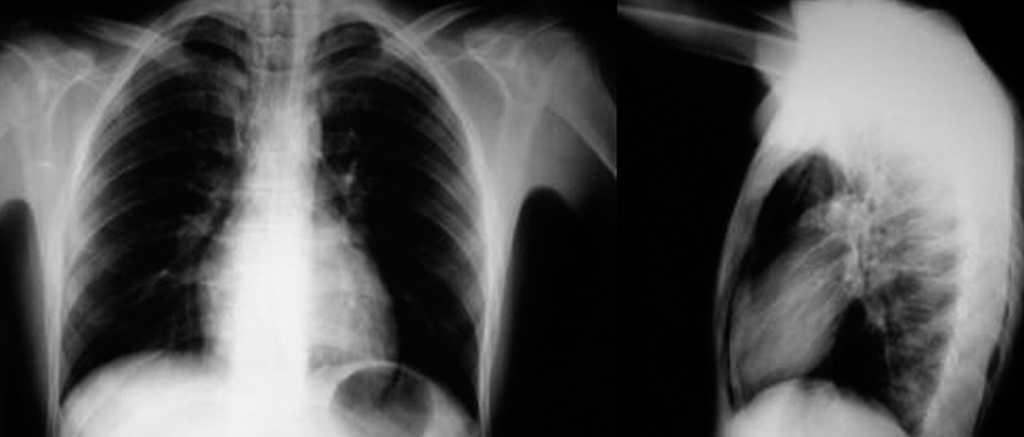

En cuanto al síndrome clínico de los pacientes a su llegada a urgencias, se han dividido los hallazgos en 2 tablas de resultados: en la tabla II se recogen los síntomas y signos que presentaron, y en la tabla III los antecedentes personales de interés y factores desencadenantes del episodio agudo. El síntoma más frecuente de presentación fue el dolor torácico (27%), seguido de su asociación con disnea (19,4%) y de la disnea aislada (20%). En cuanto a los signos semiológicos, no destaca ninguno por su elevada frecuencia. Muy infrecuente fue la recogida del signo de Hamman (5%). Entre las pruebas complementarias, destaca que no hubiera alteración de los valores analíticos en el 94,4% de los pacientes, frente a una discreta leucocitosis en 2 pacientes con neumonía. Además, el 100% de los pacientes se diagnosticaron por radiología simple de tórax (posteroanterior y lateral), sin necesidad de recurrir a más pruebas de imagen en ningún caso (fig. 1). El seguimiento radiológico del proceso, hasta su resolución, también se hizo por radiología simple.

Fig. 1. Radiografía posteroanterior y lateral de tórax: signos de neumomediastino espontáneo.